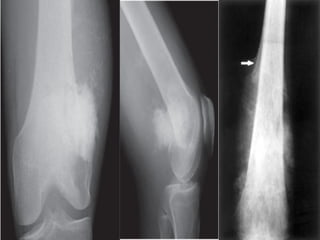

OSTEOID MATRIX

Cloud-like bone formation in

osteosarcoma.

Notice the aggressive, interrupted

periosteal reaction

Trabecular ossification pattern

in osteoid osteoma.

Notice osteolytic nidus (arrow).

Wide zone of transition indicates malignancy or infection or

eosinophilic granuloma

An ill-defined border with a broad zone of transition is a sign of aggressive

growth It is a feature of malignant bone tumors.

There are two tumor-like lesions which may mimic a malignancy and have to be

included in the differential diagnosis. These are infections and eosinophilic

granuloma